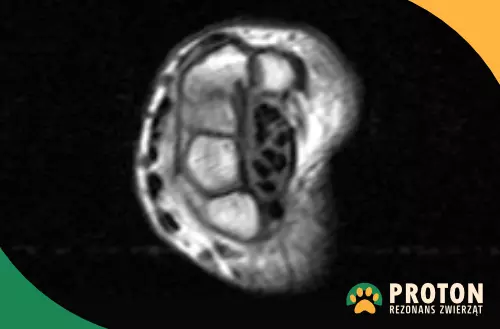

Rezonans weterynaryjny nadgarstka - zdjęcia

Obraz RM łapy

Rezonans łapy